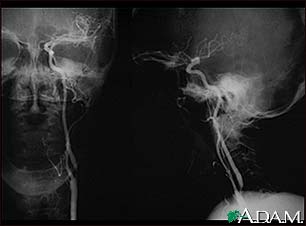

Carotid stenosis - X-ray of the left artery

Carotid stenosis - X-ray of the right artery

- Angiogram of the head to look for a blood vessel that is blocked or bleeding

- Magnetic resonance angiography (MRA) or CT angiography to check for abnormal blood vessels in the brain